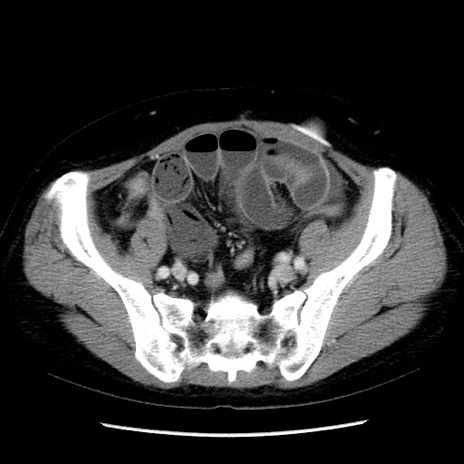

症例6(横断像)

【症例】50歳代女性

【主訴】下腹部痛

【現病歴】本日朝より下痢2回あり。 昼食を食べた後、嘔吐3回、下腹部痛認め、症状軽快せず、当院救急搬送。

最終食事:本日昼(生ものなし)。 昨日の夜、刺身を食ぺたとのこと。周囲に同様の症状の者なし。普段、排便は毎日あるとのこと。

【既往歴】卵巣癌術後(8年前に当院で卵巣摘出)

【身体所見】 意識清明、腹部:平坦、腸蠕動音→、やや硬、下腹部自発痛・圧痛あり、反跳痛あり、筋性防御なし。

【データ】WBC 16000、CRP 0.01